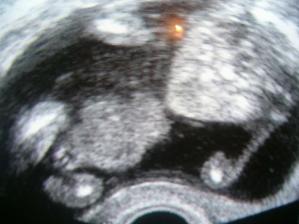

7.1. první těhu kontrola a UTZ: Fufík je tam kde má být 🙂..

21.1. těhu vyšetření + UTZ..snad uvidíme Fufíkovo srdíčko..